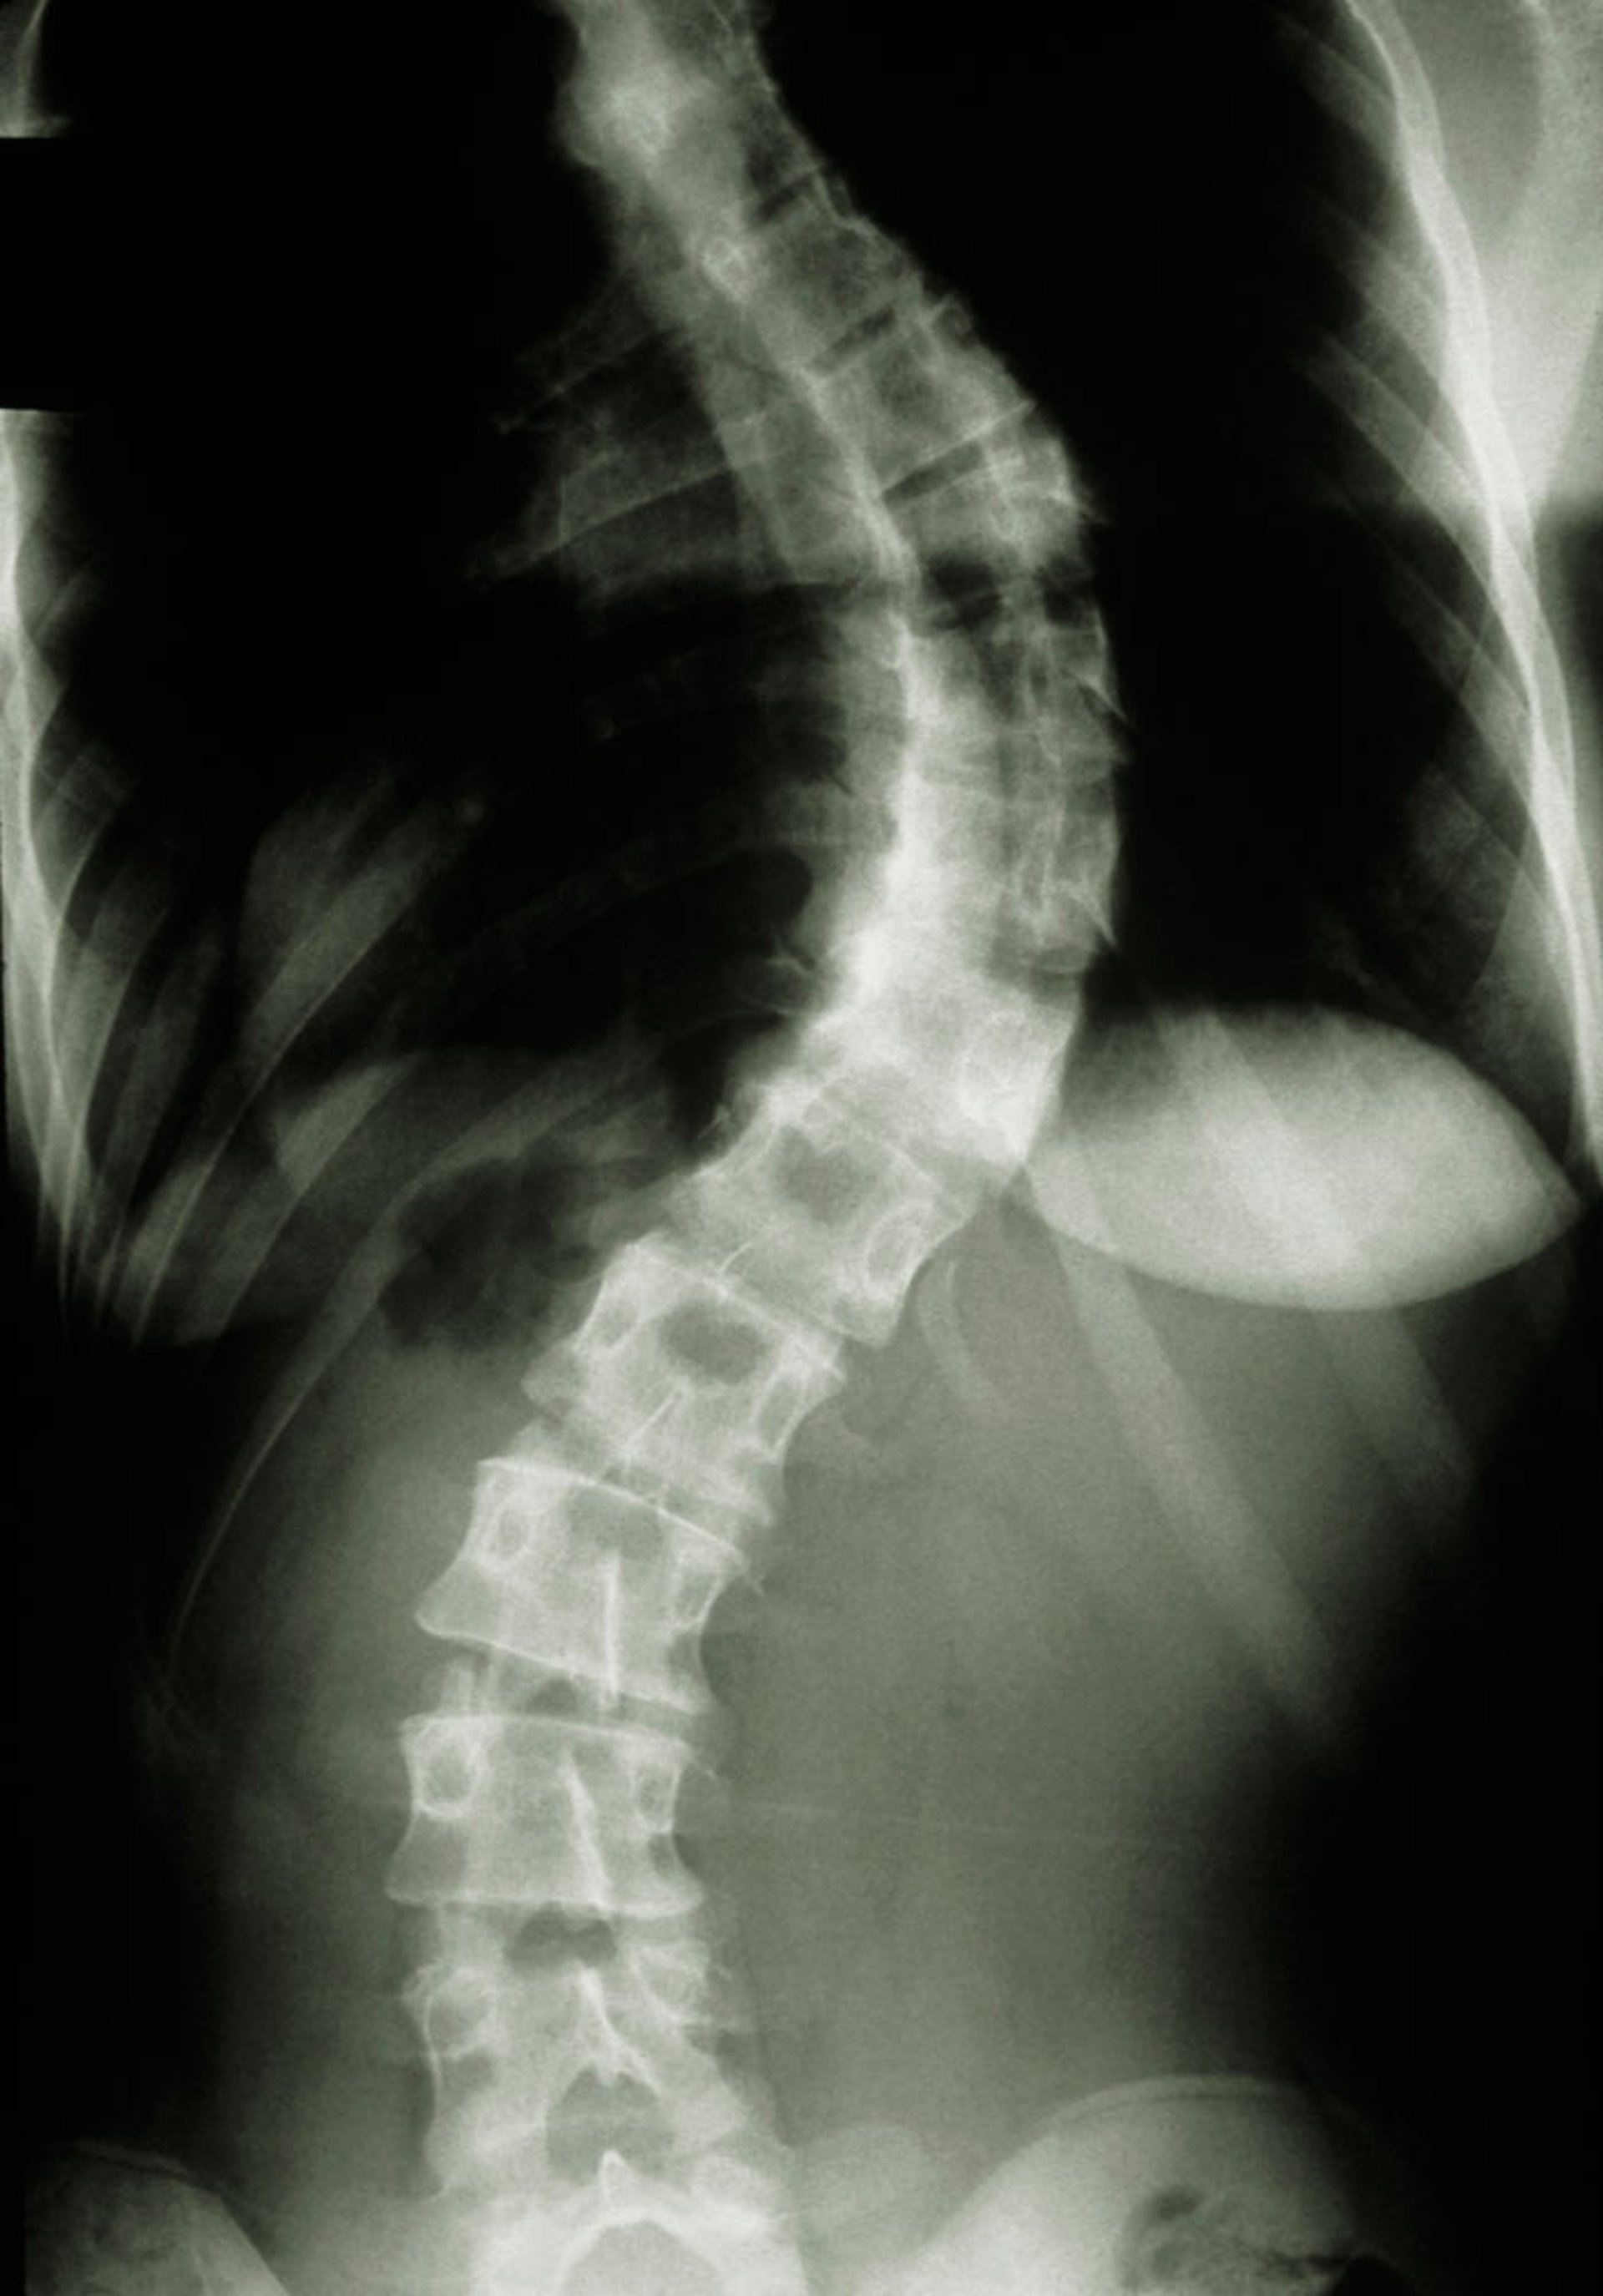

脊柱X光片(脊柱侧弯)

此X光片显示脊柱侧弯。

评估马凡综合征时,需要

科布角

20°才能计入系统评分。